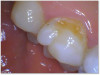

Figure 3a and Figure 3b show a failing composite with stress fractures and interproximal decay. The patient was not in a situation to do an indirect restoration, so the practitioner did a direct composite with good strength and wear characteristics until an indirect restoration could be performed. The composite used in this case is the Kerr SimpliShade Bulk Fill Packable, which in the author's experience also offers good blendability and polishability with good adaptation. Some of the discoloration interproximally is from the bleeding after the rubber dam was removed-which quickly self-resolved.

Fig 3a. A direct composite using Kerr SimpliShade Bulk Fill Packable.

Fig 3a.

Fig 3b. A direct composite using Kerr SimpliShade Bulk Fill Packable.

Fig 3b.